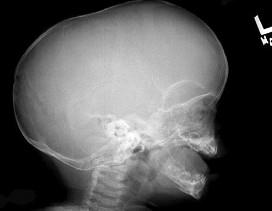

问题 男婴,10个月,头颅畸形,分离性斜视,见X线平片所示,最可能诊断为()

选项 A.颅底陷入症 B.先天性脑积水 C.显性颅裂 D.狭颅征 E.以上均不对

答案 D